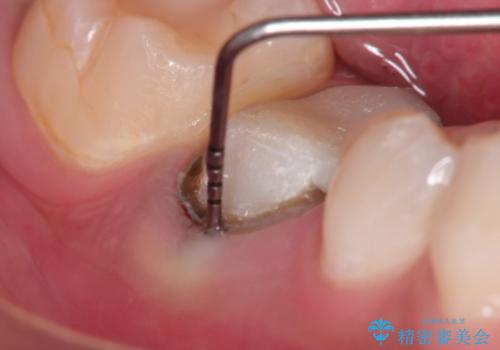

- 定期健診にて根尖に病変を認めたため治療を希望された患者さまです。

被せものを除去すると深いむし歯もありました。

歯肉に炎症がない事を確認してセラミッククラウンにて治療を行っています。

根管治療は専門医の先生に依頼しております。